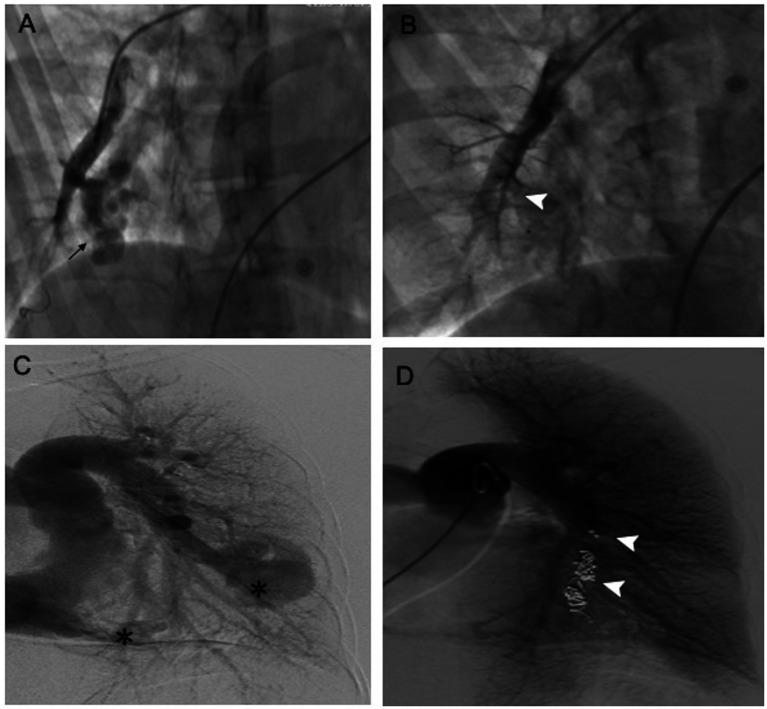

Double anterograde/retrograde approach for embolization of pulmonary arteriovenous malformation presenting with acute respiratory failure.双顺行/逆行栓塞术治疗急性呼吸衰竭伴发的肺动静脉畸形

Eur Heart J. 2023 Jul 1;44(25):2348. doi: 10.1093/eurheartj/ehad071.